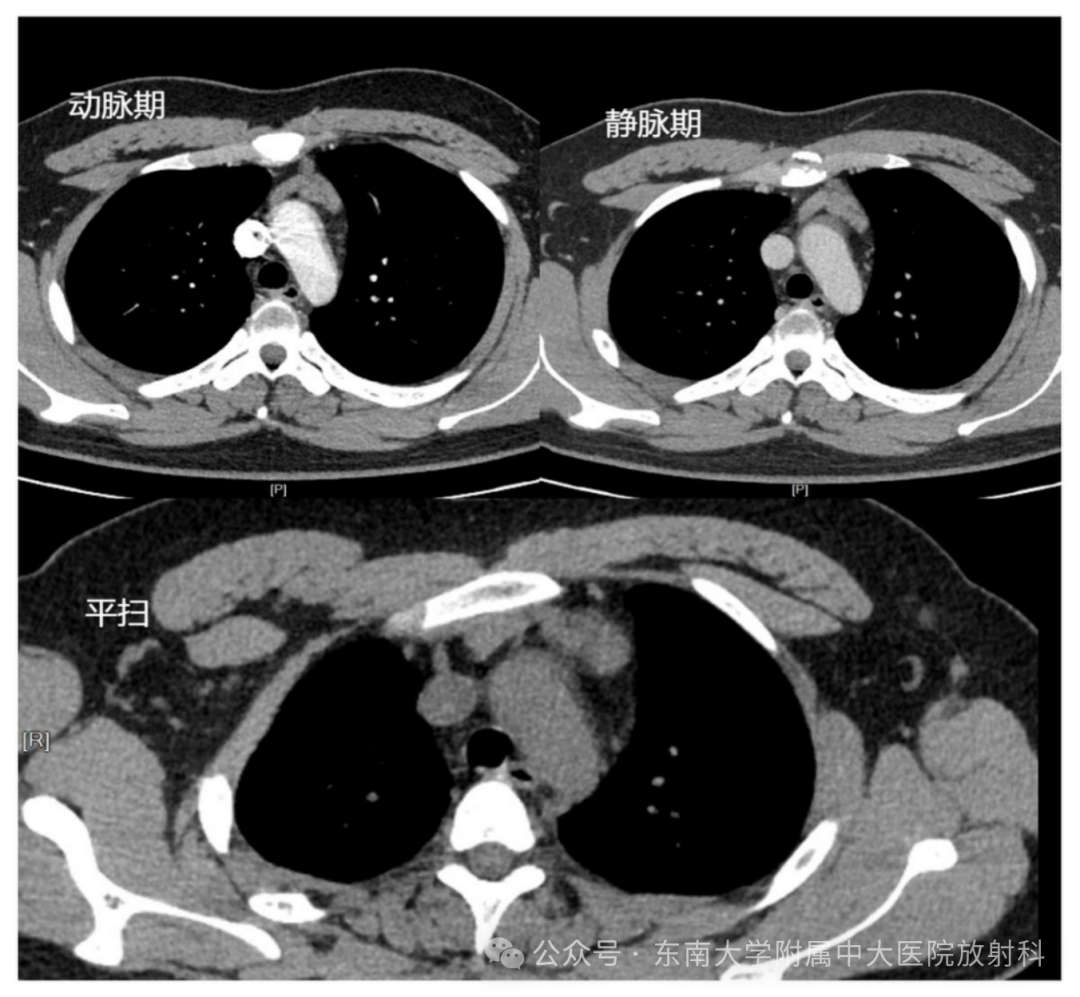

CT 影像学表现

病例2

• 性别:女   年龄:43岁

• 主诉:间断心慌、怕热半年

• 现病史:患者半年前无明显诱因下出现心慌、怕热不适,与活动及劳累无明显关系,无时间规律性。2024-01-23至我院门诊就诊,查血游离甲状腺功能异常,门诊拟“甲状腺功能亢进”收住入院。病程中,近半年体重减轻约 4kg

• 既往史:十余年前行“子宫肌瘤切除术”

• 实验室检查:

• 游离甲状腺功能:游离三碘甲状原氨酸16.0pmol/L↑;游离甲状腺素39.4pmol/L↑;促甲状腺激素:<0.00500μIU/mL↓

• 抗 甲 状 腺 过 氧 化 物 酶 抗 体(TPOAb):36.7IU/mL↑

• 抗促甲状腺素受体抗体:1.79IU/L↑

MR 影像学表现